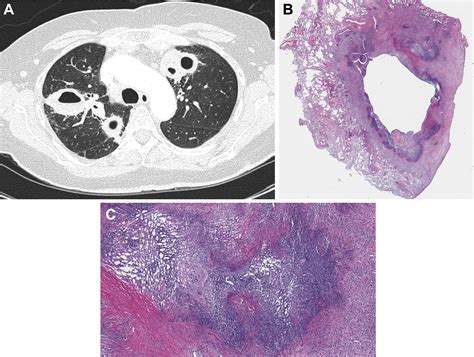

A cavitary lesion of lung is a significant radiological finding that requires careful medical evaluation. In clinical terms, a cavity is defined as a gas-filled space within a pulmonary consolidation, a mass, or a nodule. When a patient undergoes a chest X-ray or a computed tomography (CT) scan and receives this diagnosis, it often triggers immediate concern. However, understanding that these lesions can result from a wide spectrum of causes—ranging from common infections to serious malignancies—is crucial for both patients and healthcare providers to ensure accurate diagnosis and appropriate management.

At its core, a cavitary lesion of lung represents a localized area of the lung parenchyma that has been destroyed or excavated. This destruction often occurs when an area of diseased lung tissue undergoes necrosis—the death of cells—and the necrotic material is subsequently evacuated, usually through the bronchial tree. This leaves behind a hollow, air-filled void that appears distinctly on medical imaging.

Distinguishing Features on Imaging

Radiologists look for specific markers to help narrow down the diagnosis. The appearance of the cavity's wall, for instance, provides vital clues:

• Thick, Irregular Walls: These are more suggestive of malignancy (e.g., squamous cell carcinoma).

• Thin, Smooth Walls: Often point toward benign causes, such as a congenital cyst or a resolved infection (pneumatocele).

• Air-Fluid Levels: Highly indicative of a lung abscess, suggesting a collection of pus that has not yet been fully drained.